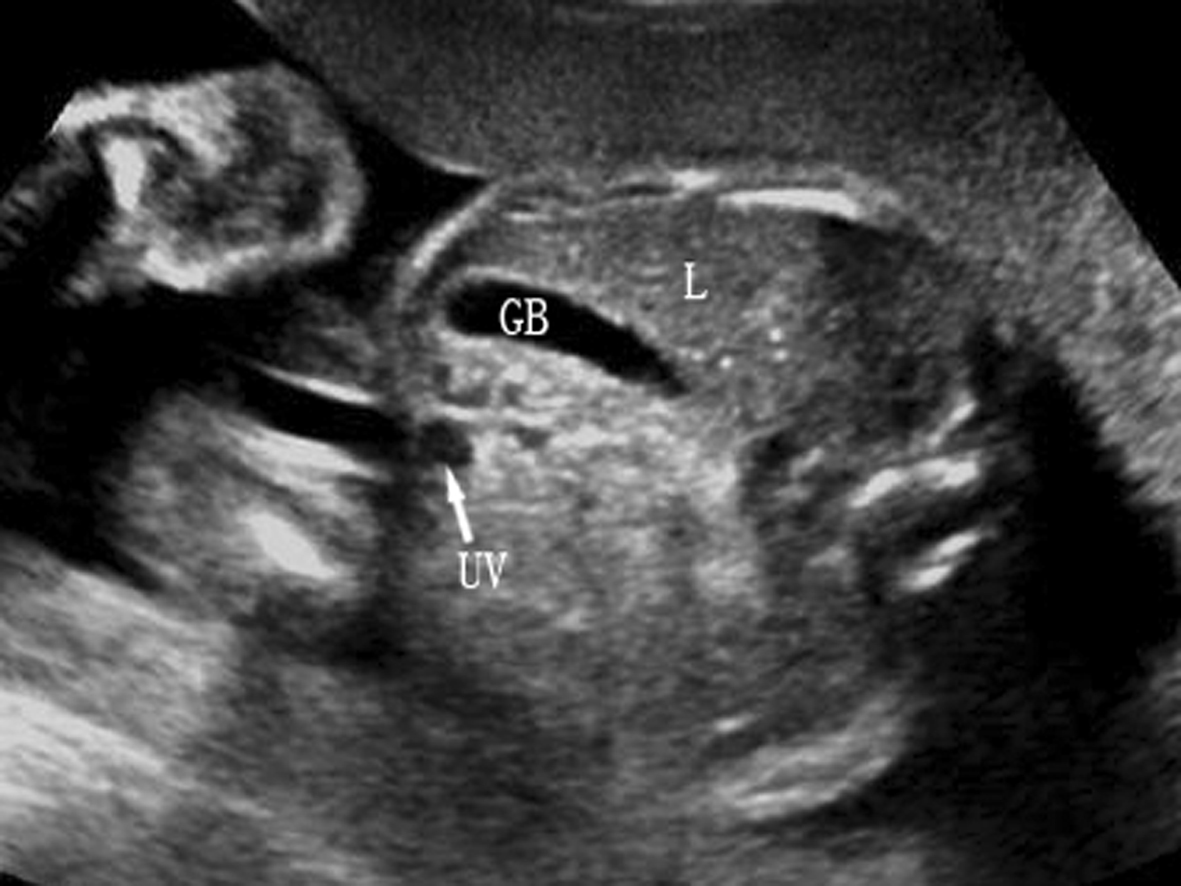

1.肝脏和脾脏 肝脏(L)是胎儿腹腔内最大的实质性器官,几乎占据整个上腹部,横断面占据腹部横截面的三分之二以上(图1A,B)。正常肝脏右叶大于左叶、上部大于下部;左外侧较尖锐,右侧圆钝;表面光滑、清晰;内部显示与成人肝脏相似的中等偏强的回声,分布均匀;第一肝门区可见门静脉进入肝脏,在第二肝门区可见肝静脉进入下腔静脉;在肝脏左叶可显示脐静脉进入肝脏(图1C)。

2.胆囊 14~16孕周后胎儿可显示胎儿胆囊回声(图2,GB)。正常胆囊长轴呈梨形,横切面呈类圆形,位于上腹部脐静脉(UV)腹腔段右侧,与脐静脉成一锐角,近腹壁但与腹壁不相连,无搏动,囊壁回声较脐静脉的管壁回声强,也较厚。当难以分辨胆囊与脐静脉时,可应用彩色多普勒超声进行鉴别。产前超声检查有时可显示胆囊结石、胆囊增大、胆囊水肿等,有报告染色体异常可能合并胆囊回声异常。

图2胎儿胆囊横切面声像图